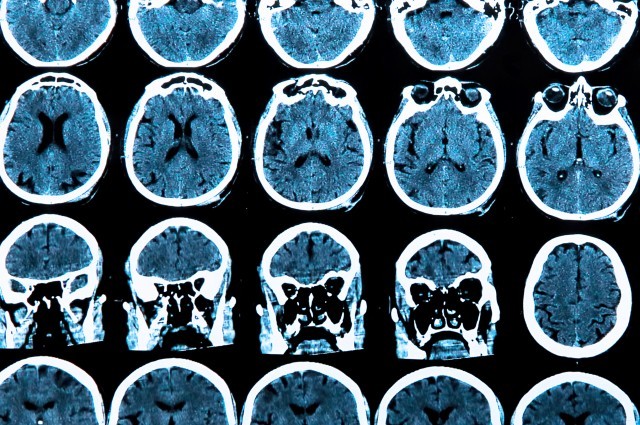

نوروسافاری| محققان کالج لندن در انگلستان موفق به شناسایی پروتئینی در خون شده اند که بسیار قبل تر از مشاهده علایم آلزایمر، می تواند بیماری را پیش بینی کند. به گزارش نوروسافاری به نقل از ایرنا، این تحقیقات که روی بیش از یکهزار پروتئین خونی در ۲۱۲ داوطلب …

نوروسافاری| ماده خاکستری مغز دارندگان گروه خونی O بیشتر از افراد دارای گروه خونی A، B یا AB است و همین مسأله از آنها در مقابل بیماریهایی مانند آلزایمر محافظت میکند. به گزارش نوروسافاری به نقل از آنا، پژوهشی که اخیرا در دانشگاه شفیلد انگلستان انجام شده است، نشان …

نوروسافاری| در یک مطالعه جدید آشکار شد افراد مبتلا به آلزایمر و دیگر انواع اختلالات ادراکی ممکن است نسبت به درد حساستر باشند. به گزارش نوروسافاری به نقل از ایسنا، «روت دفرین» یکی از متخصصان این مطالعه گفت: مشاهدات انجام گرفته حاکیست افرادی که دچار آتروفی مغزی یا روند تحلیل …

نوروسافاری| نتایج تحقیقات دانشمندان دانشگاه ملبورن استرالیا حاکی از آن است که وجود مقادیر زیاد آهن در مغز میتواند زمینهساز ابتلا به بیماری آلزایمر باشد. به گزارش نوروسافاری به نقل از باشگاه خبرنگاران، اندازه گیری سطوح آهن درون مغز افراد میتواند به شناسایی افراد در معرض خطر ابتلا به آلزایمر …